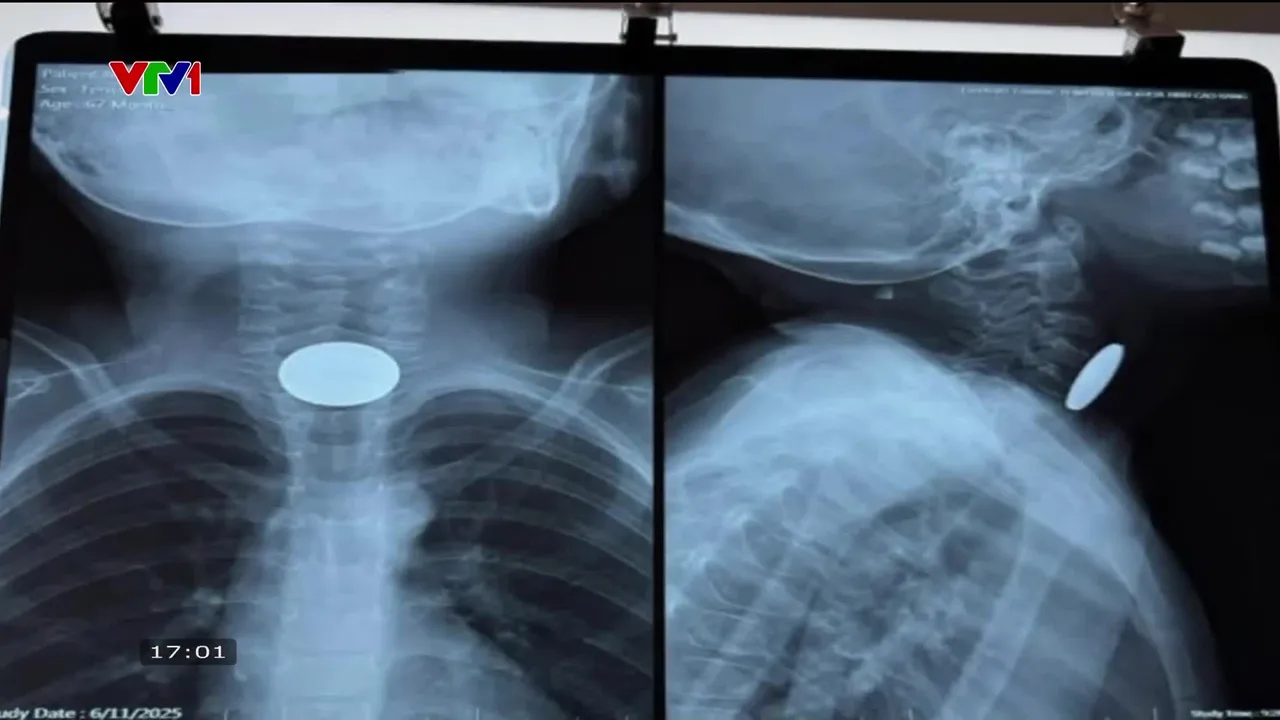

Trẻ nguy kịch do hóc đồng xu

Mới đây một bé gái 5 tuổi ở Cao Bằng đã rơi vào nguy kịch sau khi nuót đồng xu trong lúc chơi một mình.